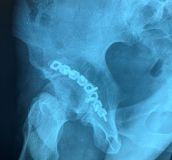

4. Posterior dislocation of the right hip with posterior acetabulum fracture in a 40-year-old male.

Treatment: 1st stage; closed reduction of the dislocation 2nd stage; open reduction of the acetabulum fracture with internal fixation

Ι. Obturator view of the right acetabulum shows the dislocation of the right hip II. Obturator x-ray right acetabulum shows the reduction of the hip, the red arrow shows the fracture III. Iliac x-ray acetabulum after the procedure shows the implant work (the patient referred to Mr. Antonios Papasotiriou who fixed the acetabulum)